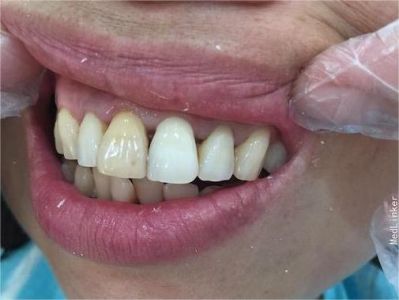

牙龈退缩牙龈萎缩露出牙根图

牙龈退缩发作于上排尖牙和磨牙处,导致牙根暴露在外,伴有牙齿松动、口臭、牙根面敏感等症状,是由于刷牙不当、牙周炎等因素引起。